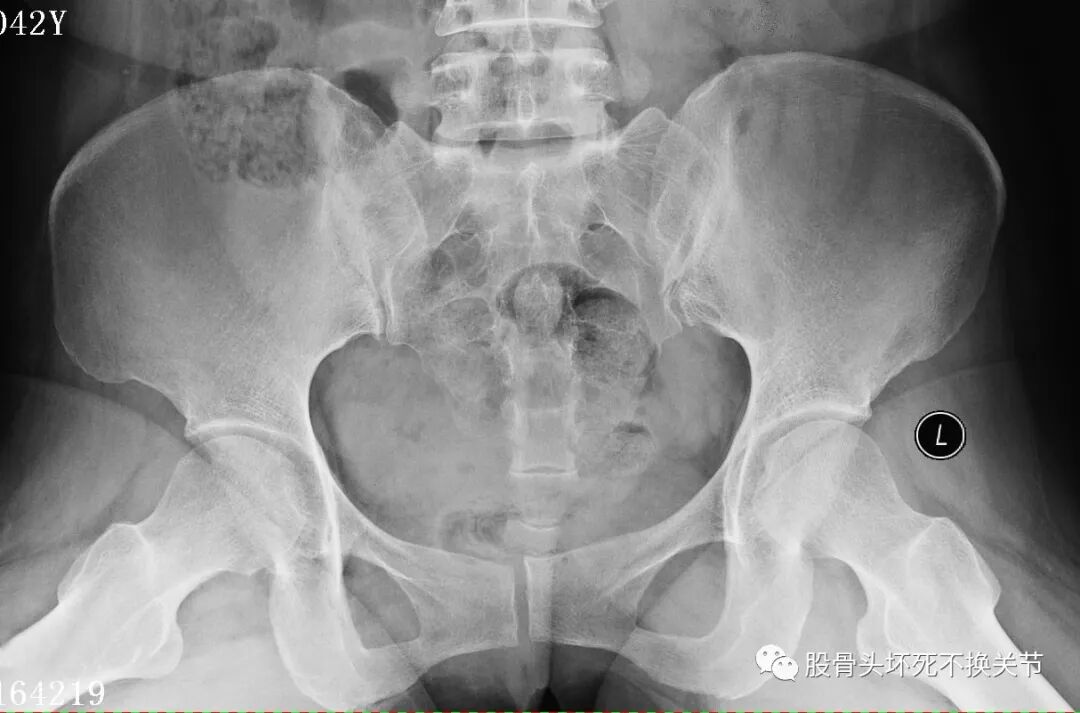

又过了半年,再次复查X线片:

股骨头除了骨密度更低之外,看不出来有特殊变化